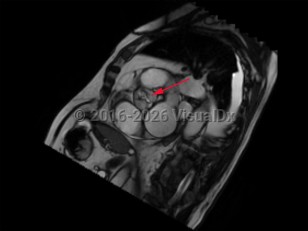

Aortic dissectionAortic dissection

Cardiac tamponadeCardiac tamponade